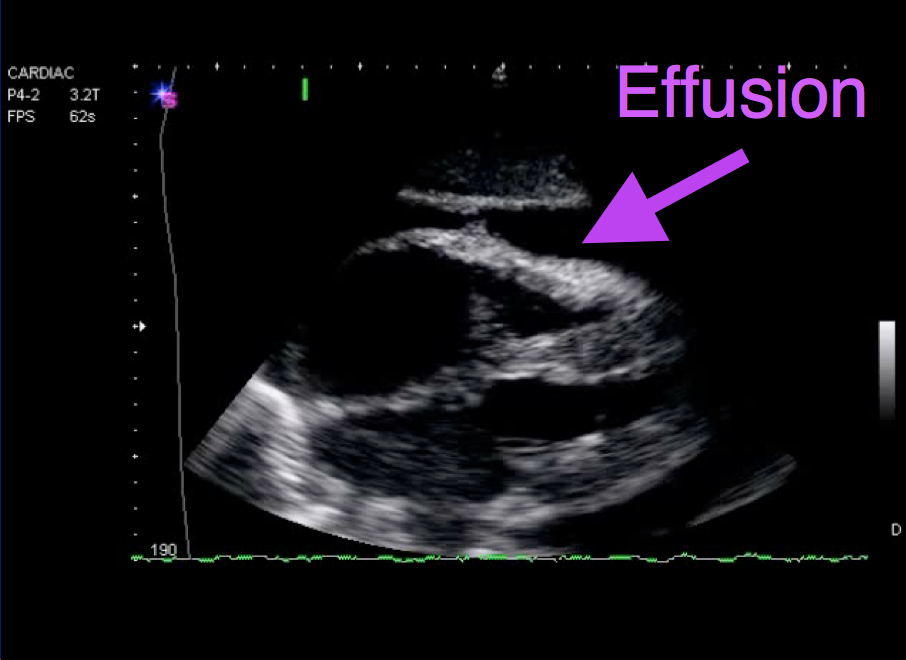

What happened to this driver in an MVA?

Pericardial effusion